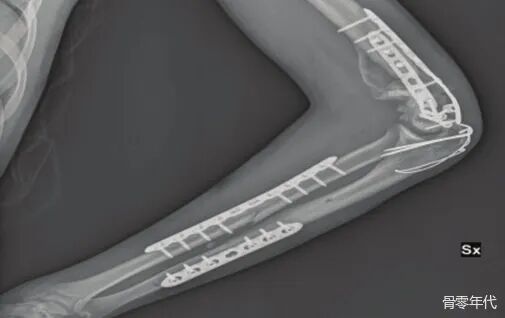

影像学表现